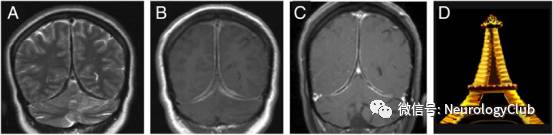

神经影像学(CT和MRI)是证实肥厚性硬脑膜炎的的主要手段,但无法明确病因。HCP常见受累部位为大脑镰、小脑幕及大脑凸面硬脑膜,而HSP以颈、胸椎椎管内的腹侧硬脊膜受累多见。CT平扫见硬脑膜增厚,呈高密度影,可伴钙化,注射造影剂后病灶强化,偶有邻近颅骨增生肥厚。MRI为本病首选检查。T1加权上表现为等信号或稍低信号,T2加权像上纤维化的硬脑膜肥厚,呈相对低信号,周围可见散在局灶性高信号,提示淋巴浆细胞浸润性炎症,病灶附近脑组织水肿罕见。增强时呈局限性或弥漫性,线样或结节状较均匀强化,部分有明显占位效应。如大脑镰及小脑幕同时强化,冠状位上形似奔驰车标记,称“奔驰征”。线样强化常提示轻度炎症,而结节状强化表明硬脑膜肥厚不均匀,多为硬脑膜纤维化合并局部强烈的炎症反应,后者对激素的治疗效果一般不如前者。Dash等发现部分肥厚性硬脑膜炎患者在增强MRI上可呈周围强化的模式,表现为中央纤维化增厚的大脑镰和小脑幕硬脑膜低信号伴外周活动性炎症区域强化,冠状位上形似夜间灯光下的法国埃菲尔铁塔,称“夜间埃菲尔铁塔征(Eiffel-by-night sign)”。这种增厚硬脑膜中心线样无强化,而两侧轨道样强化,也可称为“轨道征”。少数患者病变累及软脑膜或邻近组织,如眼眶,鼻咽部等,造成组织肿胀或形成炎性假瘤。

图6:夜间埃菲尔铁塔征。A:T2WI;B:T1增强;C:3年后复查的T1增强;D:夜间埃菲尔铁塔